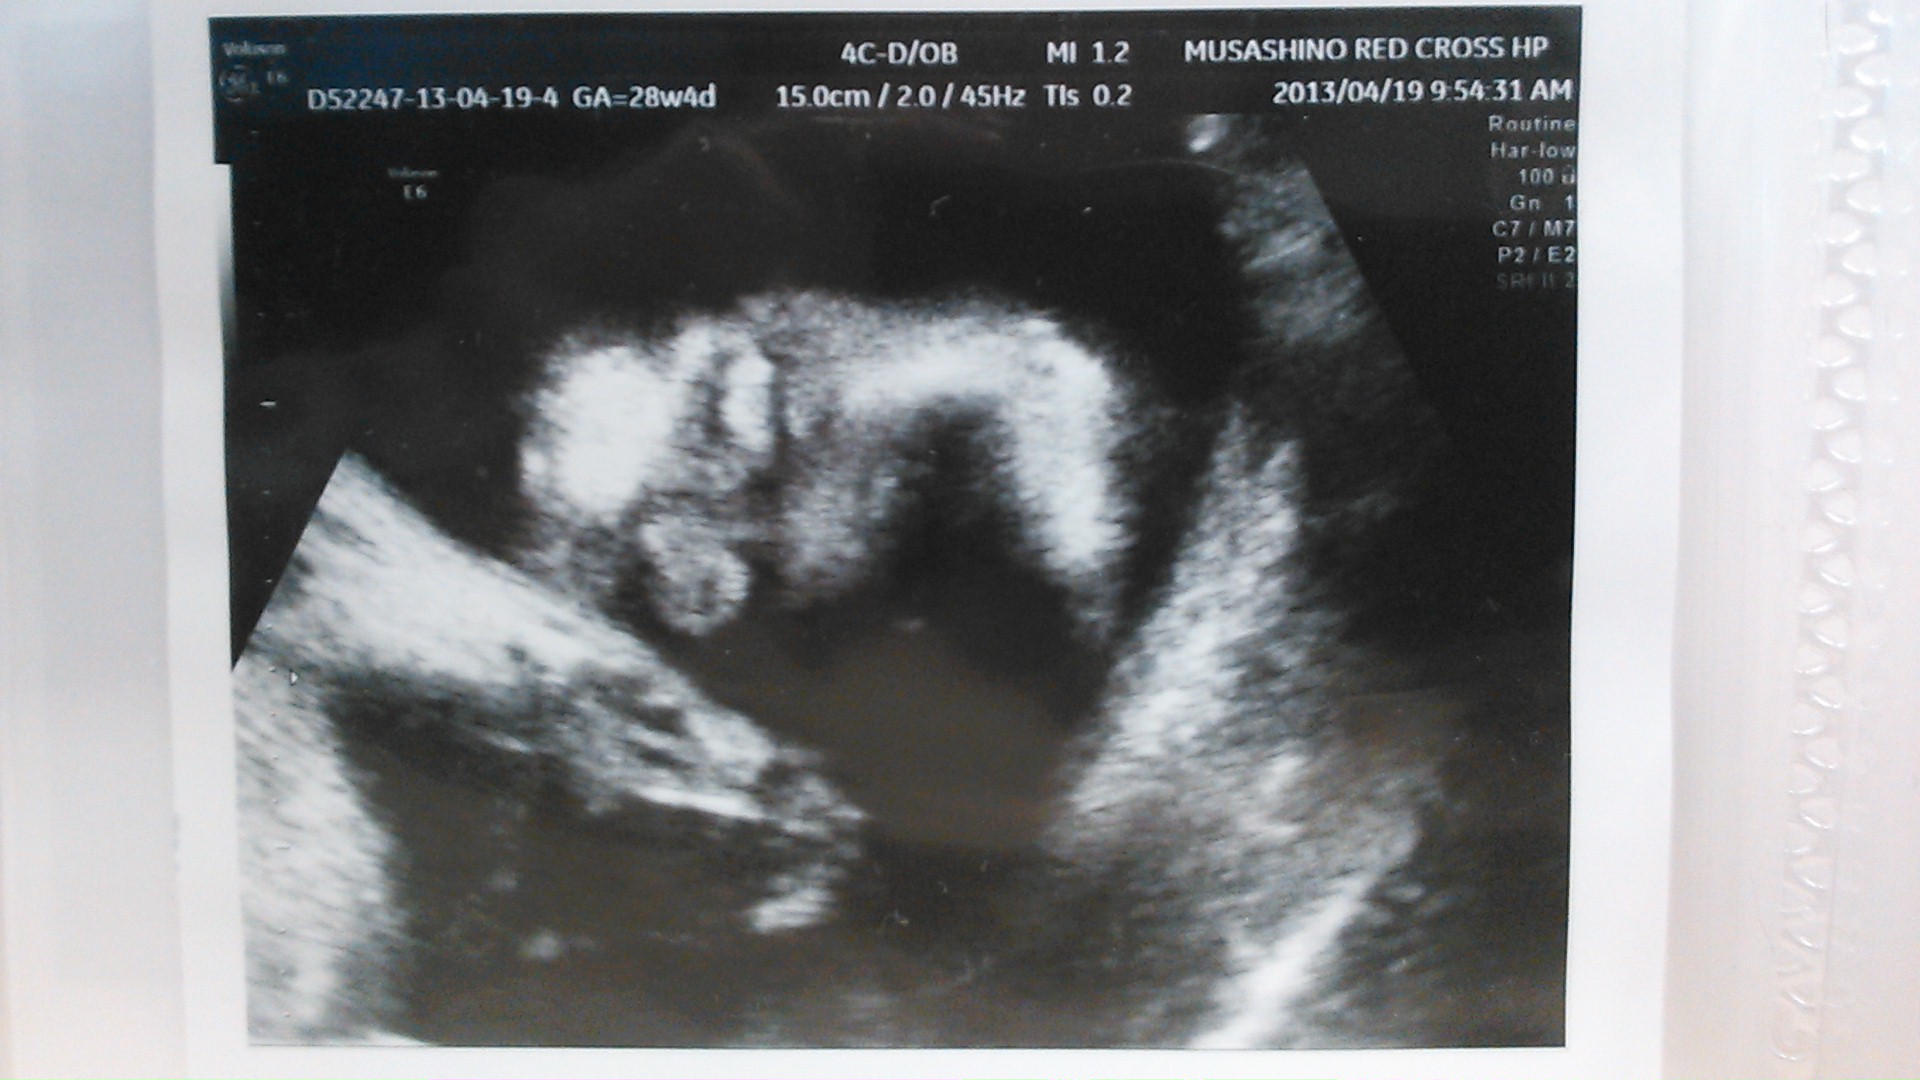

echo